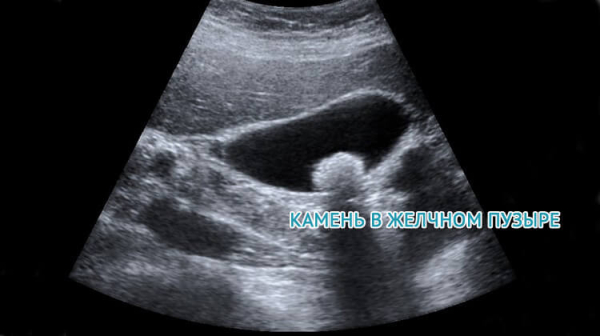

УЗИ желчного пузыря позволяет оценить его размеры, форму и структуру. С помощью УЗИ можно выявить наличие камней в пузыре или желчных протоках, определить их размеры и местоположение. Кроме того, УЗИ позволяет оценить функциональное состояние пузыря, его сократительную способность и скорость опорожнения. Если необходимо, врач может также проверить проходимость желчных протоков и оценить состояние печени.

Во-вторых, УЗИ обладает высокой диагностической точностью, позволяя обнаружить различные патологические изменения и аномалии в желчном пузыре и печени. С помощью этого метода возможно определить наличие камней в желчном пузыре и желчных протоках, опухоли, цисты, а также оценить структуру и функцию печени. УЗИ также помогает установить причину болей или дисфункций органов, что позволяет врачу правильно поставить диагноз и назначить оптимальное лечение.

- Выявление камней, опухолей и других образований;